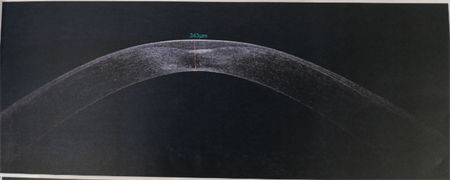

商旭敏副主任告訴我們,小蕓的右眼已經(jīng)是圓錐角膜后期,角膜厚度僅有343,再繼續(xù)發(fā)展下去,就會水腫破裂。由于圓錐角膜都是雙眼發(fā)病,小蕓的左眼此時也開始出現(xiàn)圓錐角膜的癥狀了。

▲小蕓右眼厚度343,左眼厚度523